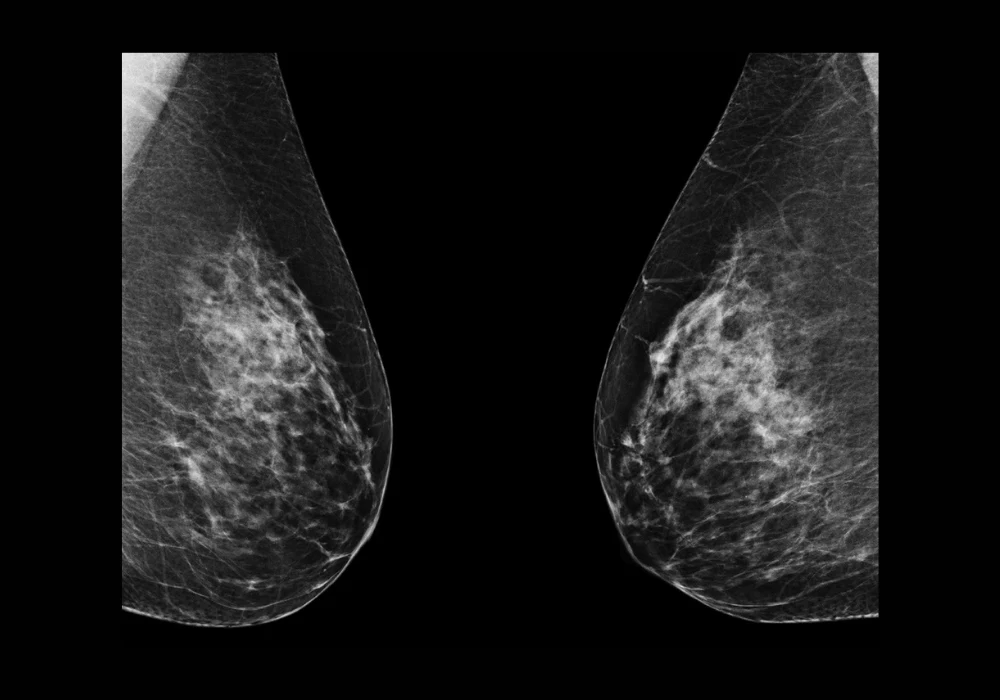

Breast arterial calcification (BAC), once considered a benign incidental finding in mammographic imaging, is now increasingly recognised as a significant marker of cardiovascular disease (CVD) risk. Its detection through standard mammograms offers a unique opportunity for dual-purpose screening in women, targeting both breast cancer and cardiovascular risk without added radiation or cost. Despite its potential, current BAC detection methods are hindered by variability and labour-intensity. A recent study introduced a novel deep learning model built on a modified U-Net architecture to automate the detection, segmentation and quantification of BAC in mammograms. The goal is to deliver a reliable tool that supports radiologists and facilitates further research into BAC’s prognostic value.

To overcome the limitations of manual and conventional automated approaches, the study developed a tailored U-Net model enhanced with a composite loss function. This function integrates Dice loss, Binary Cross-Entropy (BCE) loss and, notably, Hausdorff loss, which strengthens the model’s ability to delineate fine calcification boundaries—an essential factor in accurate BAC segmentation. The researchers trained and validated their model using a diverse dataset of mammograms from 369 women aged 60–79, acquired from multiple vendors and imaging views. Manual annotations by trained readers ensured quality ground truth data. Pre-processing steps included standardising image resolution, applying data augmentation and cropping to focus on breast tissue. This robust setup enabled the model to retain image fidelity and learn orientation-invariant features critical for generalisability across real-world scenarios.

The segmentation results demonstrated high accuracy, with Dice similarity coefficients reaching 0.90 for the training set and 0.88 for the validation set. The model’s performance surpassed previous techniques that relied on downscaled or patch-based input data. An ablation study confirmed that the inclusion of Hausdorff loss significantly improved boundary delineation, especially in complex tubular BAC structures. This advancement marked a critical step toward achieving precise segmentation essential for accurate mass quantification.